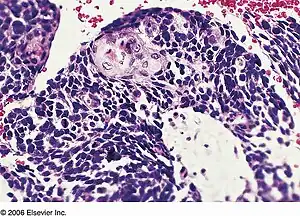

Combined small cell lung carcinoma containing a component of squamous cell carcinoma | |